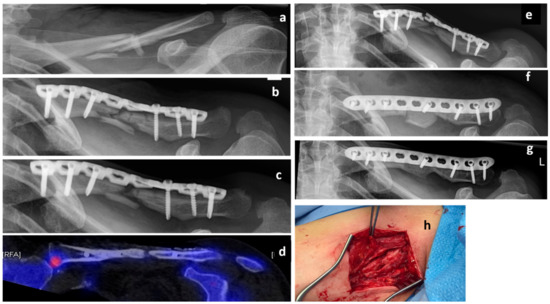

A 50-year-old female Caucasian patient (body mass 66 kg; height: 165 cm; BMI: 24.2 kg/m2) presented with a multifragmentary fracture of the left clavicle (AO 15.2C, non-dominant arm) after a bicycle accident (Figure 2a). Due to fracture comminution and shortening of the clavicle of more than 2 cm, an operative treatment was indicated. The patient was treated with an open reduction and internal fixation (ORIF) and plate osteosynthesis (LCP Reconstruction Plate 3.5, DePuy Synthes, USA) (Figure 2b). Serial X-rays during the first 6 months showed no radiological signs of union and the patient was diagnosed with an atrophic delayed union. She was referred for osteological treatment (Figure 2c). Due to inadequate Vitamin D levels and low calcium intake, both were supplemented. There were no further predisposing factors for nonunion. The radiological analysis showed a lack of contact between the bony fragments (Figure 2c. However, the patient was pain-free and, therefore, the decision against further surgery was made. A treatment with teriparatide was initiated. Subsequent biomarker analyses revealed a 61% increase in P1NP and a 208% increase in Beta CT-x after 3 months of treatment. However, there were no radiological signs of union. A single-photon emission computed tomography (SPECT-CT) after 11 months of teriparatide treatment showed no biological activity at the fracture zone (Figure 2d). Consequently, the patient was informed about the high risk of implant failure and low chance of fracture healing. Due to the fact that she was still pain-free and showed no signs of relevant impairment in the activities of daily living, she decided against an operation. As expected, the patient presented with plate failure 18 months after the initial surgery (Figure 2e). The plate was removed, and an ORIF with autologous tricortical iliac bone graft (LCP 3.5 mm Plate, DePuy Synthes, USA) was conducted (Figure 2f). The teriparatide treatment was continued. The further course was uneventful and clinical and radiological bone union was achieved 6 months postoperatively (Figure 2g).

Figure 2. Case 2, x-rays presenting the initial clavicle fracture (a), after open reduction and internal fixation (ORIF) (b), and in the presence of a delayed union 6 months after trauma (c). A single-photon emission computed tomography (SPECT-CT) scan showing a lack of biological activity at the fracture zone 17 months after trauma (d). X-rays of implant failure 18 months after trauma (e), postoperative x-ray after revision osteosynthesis with tricortical iliac bone graft (f), as well as final result 2 years after trauma (g). Intraoperative photographs and showing the atrophic nonunion (h).